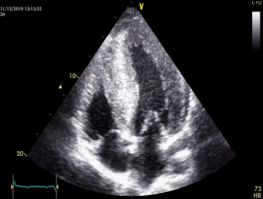

Ecocardiograma transtoracico con el mejor equipo de la región

Ecocardiograma tranesofágico

• Ecocardiografía